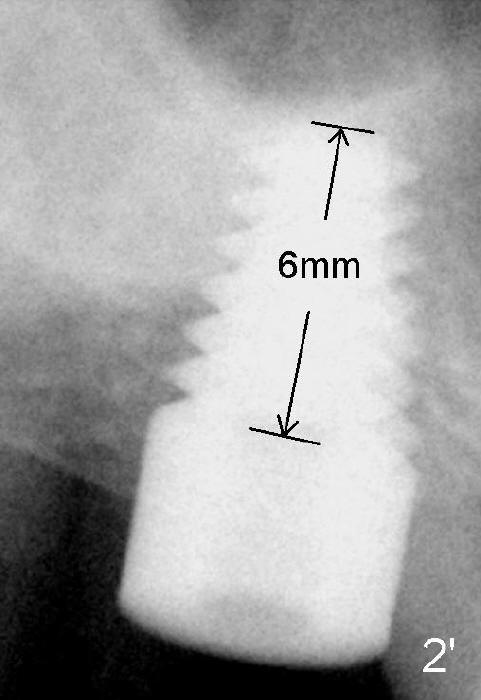

Mr. Kong is 43 years old. He has perio disease, for example #4 (Fig.1). The bone loss may be related to traumatic occlusion. The teeth #2, 14, and 15 are missing. Our primary goal is to restore these missing teeth as soon as possible. The bone height at the site of #2 is 5.8 mm. The Hounsfield units in the oral cortex, medullary and sinus floor are 400, 200 and 500, respectively. A trephine bur with outer diameter of 4 mm was used to start osteotomy (1,2). Probably due to limited access and dense bone, the trephine bur penetrated bone approximately 2 mm. A 2 mm pilot drill was used for further penetration, followed by 2.5-4.0 mm Bicon reamers for cylindrical osteotomy. A 4.5x11 mm tapered tap was used for bone expansion and sinus lift, followed by 5x11 mm tap (Fig.1). At higher magnification, it appears that the sinus floor had been lifted (Fig.1': *). A six by eleven mm tap was used. The apical end of the osteotomy felt to be intact and solid with a slender surgical curette. There was no sign of sinus membrane perforation, as confirmed by nasal blowing test. Harvested bone (from trephine bur and reamers) was pushed as apical as possible. A 6x11 mm implant was placed (Fig.2). It seems that taps/implant-related sinus lift increases the bone height to about 8 mm (Fig.2'). The thread portion of the implant is 6 mm. It appears that the 5x11 mm tap (Fig.1) and the 6x11 mm implant (Fig.2) invade the distobuccal apex of the first molar (*). Clinically there was some distance between them. Preop CT (axial section) may show the point (Fig.3: red circle stands for the implant; *: distobuccal apex of the first molar). The patient returns to office for follow up 1 week postop. The wound is healing normally around the stable implant. There is no percussion tenderness of the tooth #3. No bone resorption is observed 5.5 months postop (Fig.4), 7 months (Fig.5, Jan, 2015), 3.5 years (Fig.6) or 5 years 1 month (Fig.7) post cementation. At #14, bone height is 1-2 mm. Implant placement with sinus graft fails.